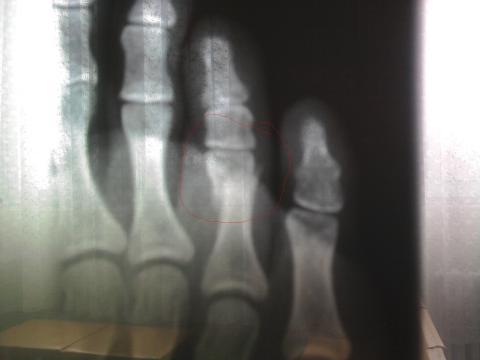

Před více než měsícem mi spadly na nohu štafle, doktor řekl, že to je pouze naražený, ale po měsíci je prst stále oteklý a bolí. Byla jsem znova u doktora a i když jsem laik, tak se mi zdá, že je na rentgenu zlomenina. Doktor však nic neříkal. Na fotce je dva dny starý rentgen, jedná se o druhý prst z prava. Prosím o Váš názor

Dobrý den,Můžete prosím nahrát fotku na některý inter. server ve vysokém rozlišení a poslat odkaz. Dle této fotky se problém těžko posuzuje, ale s vysokou pravděpodobností jde opravdu o frakturu.